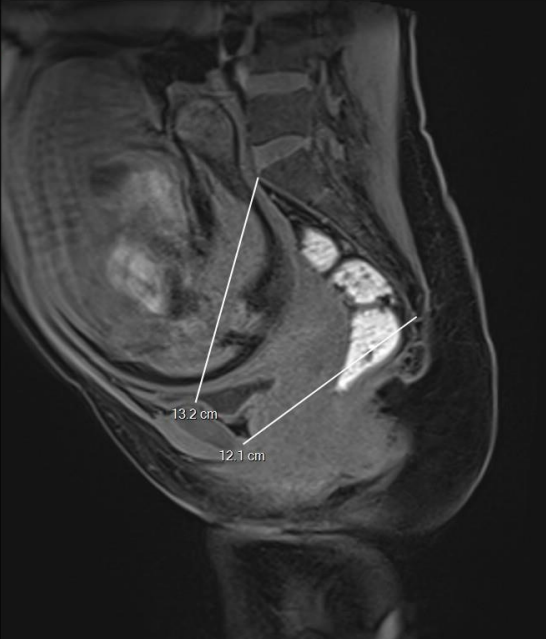

- Plan sagittal médian permettant de mesurer l’espace entre la symphyse pubienne et le promontoire sacré, puis entre la symphyse et la jonction sacro-coccygienne ;

Sur la coupe sagittale médiane :

- Distance promonto-rétropubienne (obstetric conjugate) ;

- Distance sous-sacro sous-pubien (sagittal outlet).